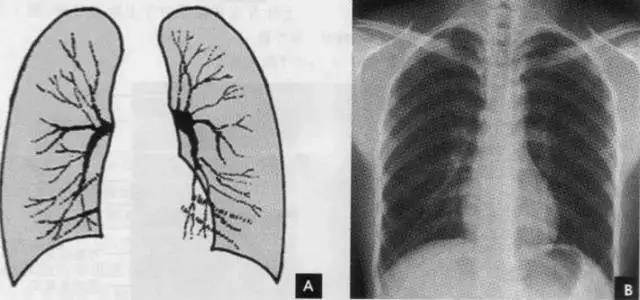

2.肺纹理

肺纹理为自肺门向肺野呈放射状分布的树枝状阴影,它主要是肺动脉的投影,肺静脉、支气管和淋巴管也参与形成。肺纹理由肺门向外围延伸,逐渐变细,至肺野外带渐细小而稀少,距侧胸壁内缘约1cm范围内的肺野基本无肺纹理可见(图下图)。